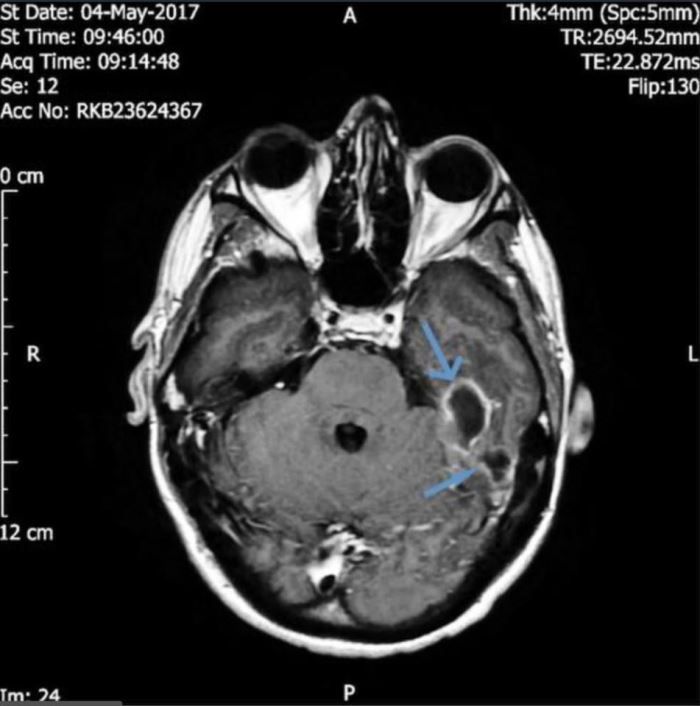

The man was taken for a CT scan on his brain, which revealed two pus-filled abscesses in the bones at the base of his skull.